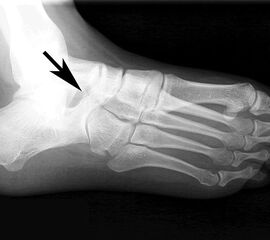

Frakturiertes Os peroneale. Das proximale Fragment ist am Fußaußenrand neben dem Calcaneus erkennbar, das distale Fragment liegt noch in Höhe des Cuboidtunnels.

Abbildung 5

Die klassischen Röntgenaufnahmen des Sprunggelenks in zwei Ebenen und des Fußes in drei Ebenen unter Belastung dienen vor allem dem Ausschluss der verschiedenen Differentialdiagnosen. Weiterhin können knöcherne Verletzungen der Gleitrinne oder auch eine Ruptur der Peroneaus longus Sehne mit disloziertem Os peroneum dargestellt werden. Besteht der Verdacht auf ein kleineres Knochenfragment oder besteht gleichzeitig eine Fraktur, so kann in Ergänzung ein hochauflösendes CT durchgeführt werden 7.